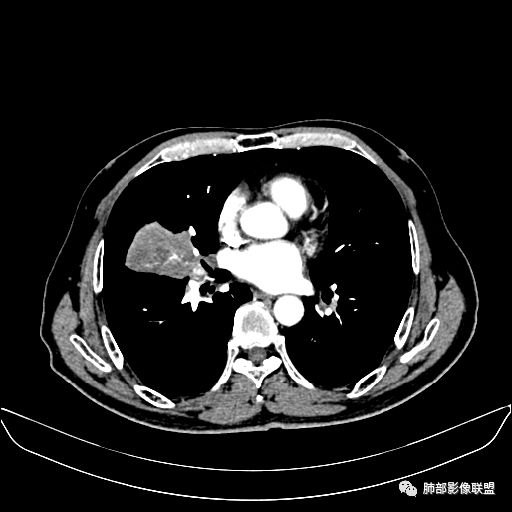

静脉期

老年男性,因“咳嗽咳痰1月余。”入院。病程中咳嗽咳痰,咳黄白痰,间断咯少许鲜红色痰血。PPD阳性。胸CT:右肺中叶外侧段支气管管腔阻塞,大片实性病变,病灶边缘光滑,部分边缘膨隆,可见分叶,肺门及纵隔可见肿大淋巴结,并可见钙化。增强可见病灶明显强化,而且延迟强化明显,病灶内多发低密度区,内见血管影,血管变细、部分血管破坏。考虑恶性病变可能性大,鉴别慢性肉芽肿性病变。

胸CT:跨叶大肿块,主体在中叶,右中叶外侧段支气管阻塞,病灶部分边缘膨隆,可见分叶,部分边缘平直,肺门及纵隔可见肿大淋巴结。增强病灶不均匀强化,延迟强化明显,病灶内多发低密度区,内见血管飘浮,部分血管变细、模糊。考虑:恶性病变可能性大,大细胞?淋巴瘤?鉴别慢性肉芽肿性病变。

吴婧老师和南边老师都对该病例进行了深入分析。从支气管管壁的增厚,支气管狭窄后扩张,支气管粘液栓,病灶形态,到病灶不均匀强化及坏死彻底,到周边病灶及肺组织空气的潴留,加之纵隔内淋巴结肿大伴钙化等等,都支持慢性炎性病灶,尤其是结核。

墨西哥仙人掌征---结核        影像上结核灶,粗大的均匀枝干,推测是支气管囊状扩张引起的,在非支气管区,形成圆形坏死囊群;如果这些坏死比较稀薄,又遇到扩张支气管,就会形成粗大的“墨西哥仙人掌”。结核引起的支气管近端炎症纤维化,可以造成支气管阻塞,从而将干酪样坏死物封堵在管腔内。仙人掌主干内部应该是干酪为主,稀薄的,具有流动性,时间久了会出现钙化。

结核坏死与鳞癌鉴别有一点是结核坏死没有方向性,鳞癌有。鳞癌靠近支气管近端部分,血供容易维持,不易坏死,所以坏死靠外侧。而结核干酪样坏死,把一定体积的流动性坏死物,包裹起来,什么形状最省料?坏死物包裹,表面积最省的自然是圆球形,而遇到支气管,坏死物一多,就把支气管撑大了。包裹物是就地取材,扩张的支气管就成了包裹结构。